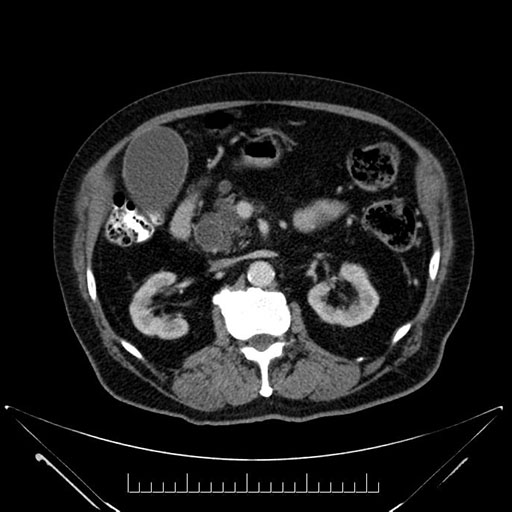

Whipple (pancreaticoduodenectomy) [case 7]

Imaging Analysis

Look through the patient's CT scan to identify any areas of concern for the necessary procedure.

Based on your CT findings, which issue(s) would give reason for "planned slowing down moment(s)" in this case?

Considering a standard Whipple procedure, what step(s) of the operation would you do differently in this case?